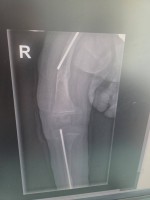

Madzia choruje na wrodzoną łamliwość kości typu III (osteogenesis imperfecta) – rzadką, genetyczną chorobę tkanki łącznej, która powoduje skrajną kruchość kości. Złamań doznała już w życiu płodowym, a jej organizm nie produkuje kolagenu. Choroba jest nieuleczalna, a leczenie ma charakter objawowy i obejmuje stałą rehabilitację, liczne operacje, stabilizację kości oraz specjalistyczną farmakoterapię. Dziewczynka ma za sobą już kilka poważnych zabiegów oraz kilkanaście podań leków wzmacniających kości. Przed nią kolejne operacje i intensywna fizjoterapia, bez której trudno byłoby myśleć o większej samodzielności.

Foto: Licytacje dla Madzi Sulki.